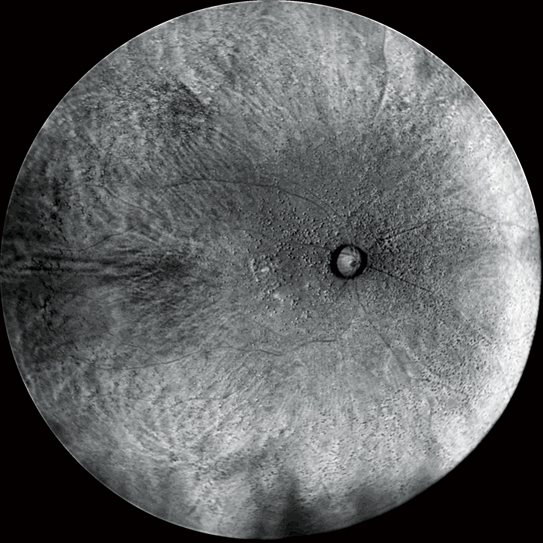

Retro后照模式

Retro后照模式是一種富有特色的無創檢查技術,用于檢測脈絡膜的病理改變。

這種成像方式通過采集玻璃膜疣、水腫及其他細微的脈絡膜視網膜病變引起脈絡膜中散射的紅外光來立體的呈現病灶。